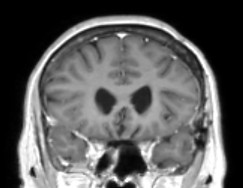

Falx cerebri meningioma

Meningioma starp smadzeņu puslodēm pirms operācijas

Pēc operācijas meningiomas vairs nav